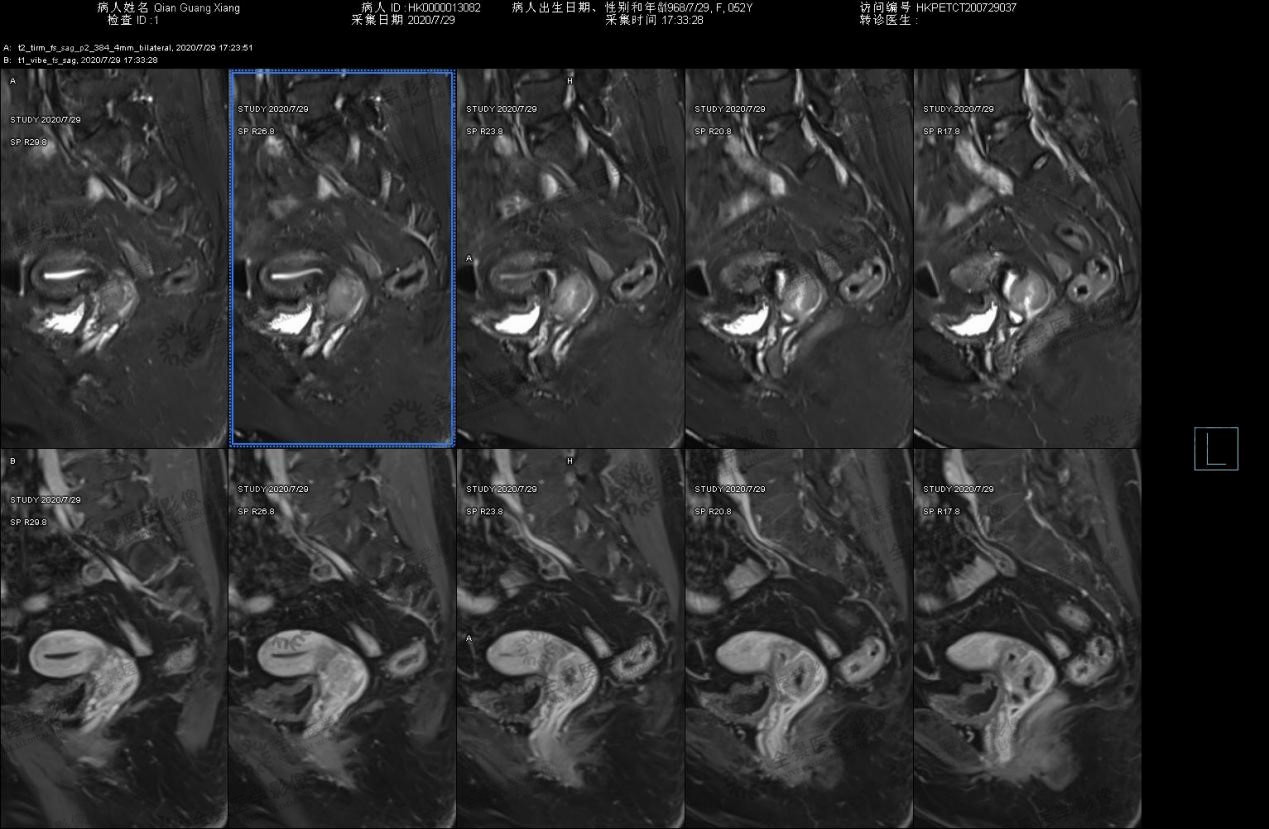

病史:女 52阴道分泌物多半年。2020-7-13B超:颈管内实质占位 血供丰富,2020-7-22宫颈活检:低分化腺癌 腺鳞癌待除外,HPV结果未出,为排除远处转移来诊。无慢性病史,无药敏史。

宫颈异常强化灶伴FDG摄取增高,考虑为宫颈癌,累及子宫峡部及阴道上段(右侧壁为主)。